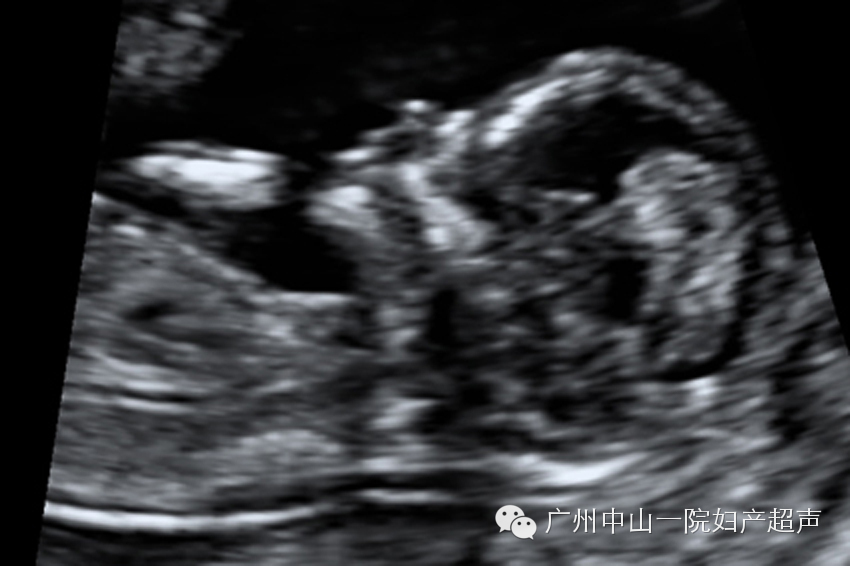

宫内妊娠13周胎儿各器官结构超声声像

这个时期,宝宝已经初见人形,头部躯干四肢可以分辨出来了,也可以看到宝宝的活动,但是由于宝宝的神经系统高级调控机制仍然没有发育成熟,所以宝宝的活动是像触电一般的全身低级电生理反射活动。但是准妈妈通常在这个时期还无法感知到胎动,只能通过超声观察。运用三维超声可以给宝宝照一张全身照,满足妈妈们的好奇心。

此次检查除了观察胎儿大体结构健全与否之外还要测量胎儿头臀长度、鼻骨长度、颈部透明层厚度(NT)、静脉导管血流频谱、三尖瓣血流频谱等超声软指标来判断胎儿有无染色体异常的风险。虽然胎儿的各系统结构已经发育完全,但是仍然太小,超声的分辨能力只能诊断部分畸形,如:无脑儿、脐膨出、腹裂、肢体残缺、淋巴水囊瘤等。此次检查还有一个重要目的就是判断双胎妊娠的绒毛膜性。双胎分为单绒毛膜单羊膜囊(MCMA),两个孩子在一个房间里;单绒毛膜双羊膜囊(MCDA),两个孩子在一个房间里,中间用一个帘子分隔开;双绒毛膜双羊膜囊(DCDA),两个孩子一人一个房间。这三者的孕期并发症风险是MCDAMCMADCDA,主要是双胎输血综合征(TTTS)和选择性宫内生长受限(s-IUGR),当然还有诸如双胎贫血多血序列、脐动脉反流胎、早产等多种。并发症会引起严重后果,甚至胎儿死亡,所以早期超声检查判断胎儿绒毛膜性对于监测多胎妊娠具有重要意义